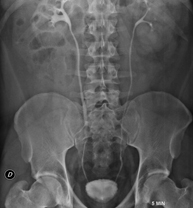

- Abdomen i pelvis

- RX Abdomen

Tècnica que usa els raigs X a través de la qual s'obtenen imatges de l'abdomen (estómac, intestí prim, intestí gros, fetge, ronyons, bufeta, pelvis òssia, etc.) per al seu estudi. - RX Columna lumbar

- Abdomen X-ray

An abdominal X-ray uses a small dose of radiation to obtain a two-dimensional image of the abdomen with its anatomical structures (stomach, small intestine, large intestine, liver, pancreas, kidneys, bladder, bony pelvis, etc.).